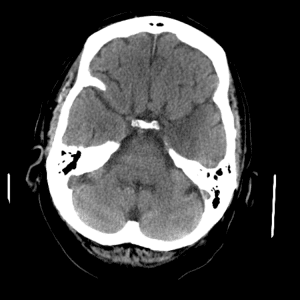

PICA infarct